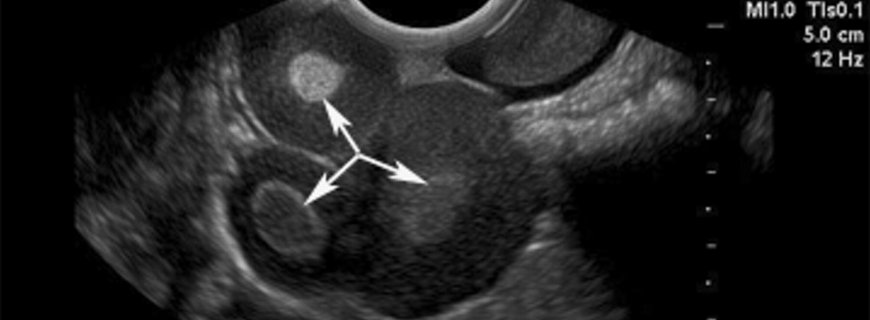

Yumurtalık Kisti Nedir?

21.10.2020

Folliküler Kistler

Korpus Luteum Kistleri